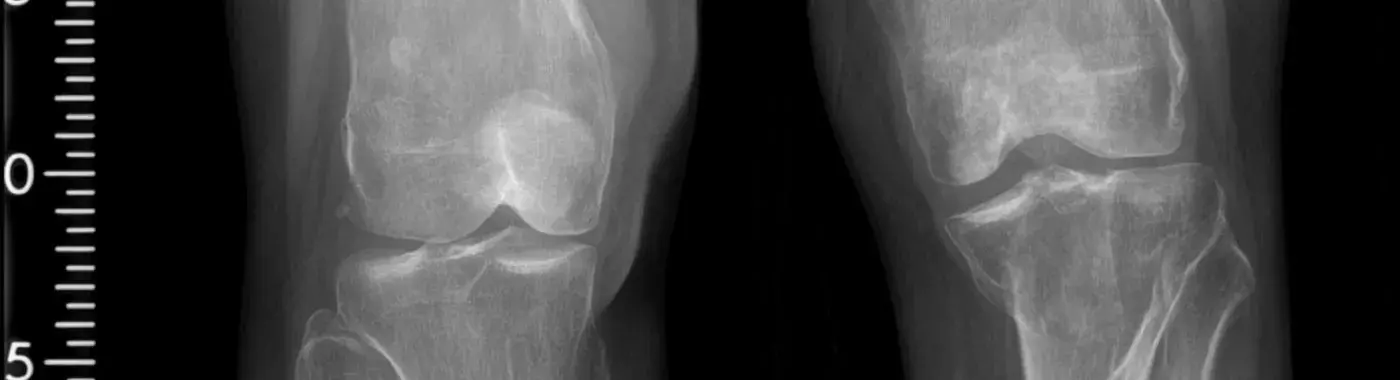

• Imaging Studies: X-rays are commonly used to visualize abnormal bone growth. In some cases, advanced imaging techniques such as MRI or CT scans may be necessary to assess the extent of HO and its impact on surrounding tissues.

Heterotopic ossification is defined as the formation of bone in non-skeletal tissues, which can occur in various parts of the body, including the hips, knees, shoulders, and elbows. This abnormal bone growth can occur after trauma, surgery, or in certain medical conditions. The bone formed in these areas is not part of the normal skeletal system and can interfere with normal movement and function. HO can be classified into two main types: traumatic and non-traumatic. Traumatic heterotopic ossification typically occurs after an injury or surgery, while non-traumatic heterotopic ossification can arise from conditions such as neurological disorders or genetic syndromes.